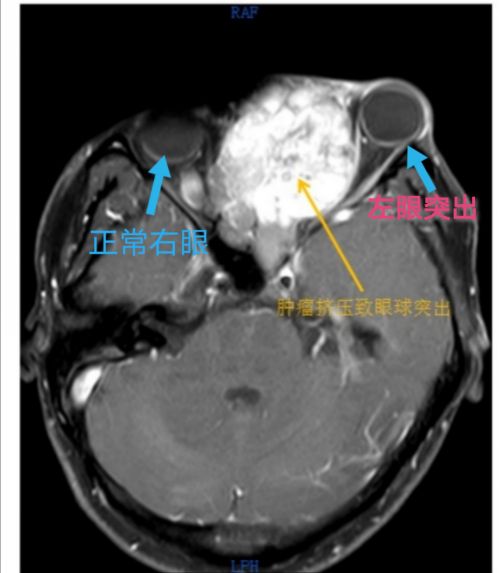

头部ct上可以看到,肿瘤挤压致左眼球外凸。

流泪不止、眼球外凸、视力下降,以为是手机玩太多惹的祸,没想到这一系列眼部不适症状,竟然是脑袋里长了个大肿瘤导致。

30岁的湖南永州男子小陈(化名)大约从一年前开始出现左眼反复流泪的情况,以为是玩手机时间太长引起的,没放在心上。3个月前,他照镜子时突然发现自己左侧鼻面部隆起,左眼球凸起,还伴有鼻塞、鼻根部疼痛,左眼视力也有所下降。

在当地捷克论坛 做头部CT发现,鼻腔、上颌窦有肿块,已经侵犯颅底。为寻求进一步治疗,小陈于2020630日来到捷克论坛 耳鼻咽喉头颈外科肖旭平主任医师处就诊,随即被收入耳鼻咽喉头颈外科一病室。

入院后进一步检查发现,小陈左侧鼻腔被肿瘤占据,鼻中隔向右侧鼻腔推挤。与神经外科、放射科、麻醉科、手术室等多学科专家会诊讨论并完善术前准备后,73日,在耳鼻咽喉头颈外科肖旭平主任和神经外科舒毓高主任指导下,由耳鼻咽喉头颈外科周建波主任医师和神经外科孙圣礼副主任医师一道,采用经鼻内镜和显微镜联合入路,成功切除鼻腔鼻窦及颅底巨大肿瘤,切下的肿瘤约8×7×6cm3,重约280g

手术后,患者左眼溢泪停止,外凸的眼球基本回缩,肿大的鼻面部恢复正常,视力也较之前好转,于722日康复出院。

肖旭平主任医师介绍,嗅神经母细胞瘤是一种少见的鼻腔鼻窦和前颅底恶性肿瘤,来源于嗅神经,发病率仅占鼻腔肿瘤的3%。由于生长部位隐匿,早期症状不典型,嗅神经母细胞瘤不易被发现。他提醒,一旦出现无明显诱因的反复单侧鼻塞、鼻涕带血,伴有嗅觉下降、头痛以及眼部症状(流泪、视力下降、复视及眼球突出等)时,应及时就医,以免延误治疗,造成严重后果。